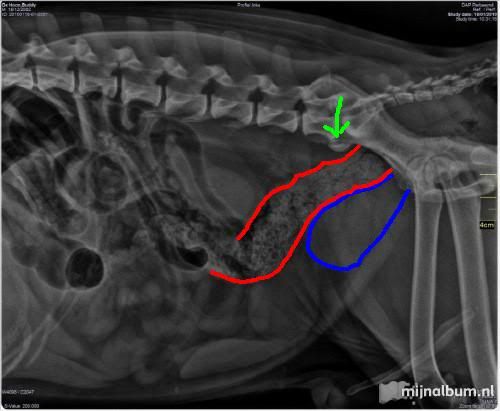

Ik heb op de fotos even aangegeven wat ik precies zie. De eerste foto:

Blauw is de prostaat, rood is de dikke darm. Groen pijltje is het 'bruggetje' tussen werveld L7 en S1. Dat bruggetje hoort niet te bestaan, maar hoeft dus niet persé pijn te geven (kan wel). De prostaat is flink vergroot, maar voor zover zichtbaar wordt de dikke darm niet dichtgedrukt. Je ziet de poep in de dikke darm zitten, maar die kan zo te zien gewoon naar buiten. Op basis van deze foto zou ik niet kunnen voorspellen dat deze hond last heeft van zijn prostaat.